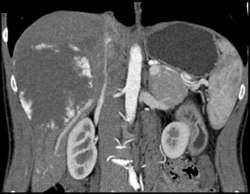

Diagnosis

Hemangioma